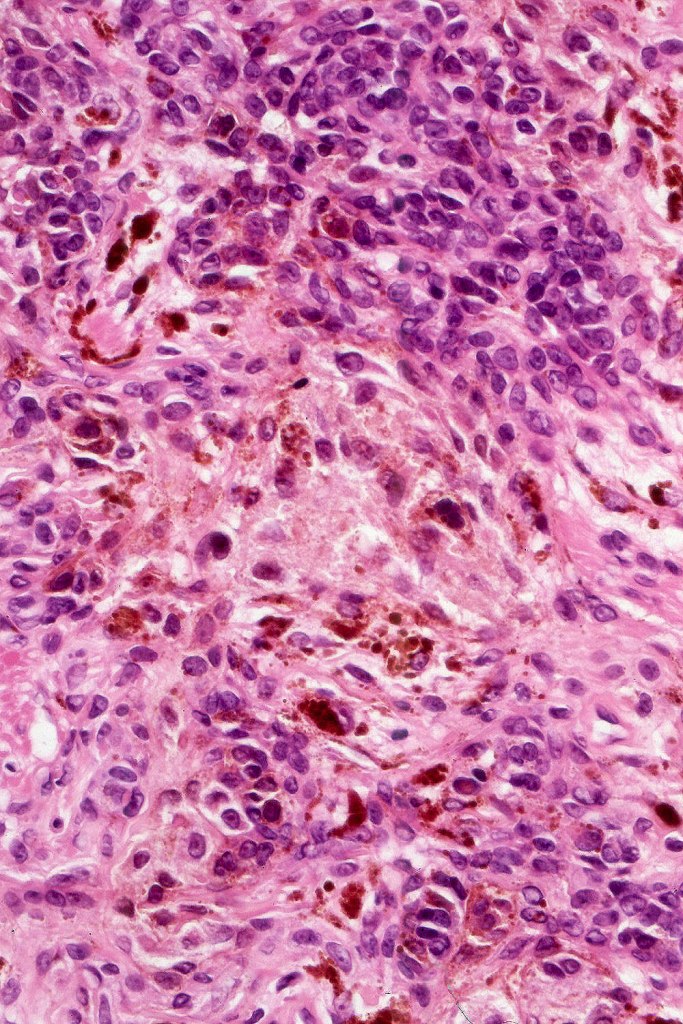

Combined congenital & blue nevus (same case as the clinical photographs coursty of Dr. Antonina Kalmykova